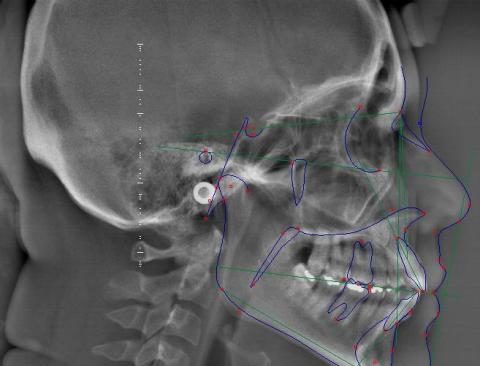

Estudio Cefalométrico

Estudio Cefalométrico Computarizado: utilizamos programas especiales de computadora, para estudiar la posición de los dientes y el crecimiento de los huesos maxilares.